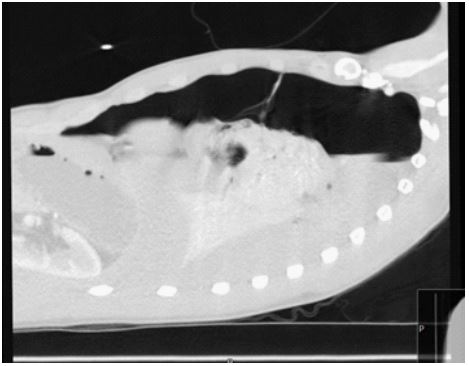

Throughout the day, his suffering worsened. This led him to visit his local GP who advised him to take analgesia and was discharged. By evening, he was increasingly breathless and restless, which led to then call the emergency services. Initial examinations by the EMS personnel revealed he was found to be tachypneic, tachycardic, and was hypotensive, however, the oxygen saturation was 91%. When he was first assessed upon being led to our ED, he appeared frightened, tachypneic, and was in pain. Upon doing a chest auscultation, it was discovered that the right chest had good air entry whereas the left had none, as well as stony dullness on the left base and resonance to percussion of the left upper lung. A chest x-ray was performed following the administration of analgesia (Figure 1), and the results of a VBG showed (pH 7.29, PCO2 7.45, PO2 2.01, CHCO3 26.3, Lactate 3.2 mmol/L, and HB 127 g/L).

Figure 1: An expiratory view showing totally collapsed left lung with fluid level indicating haemothorax